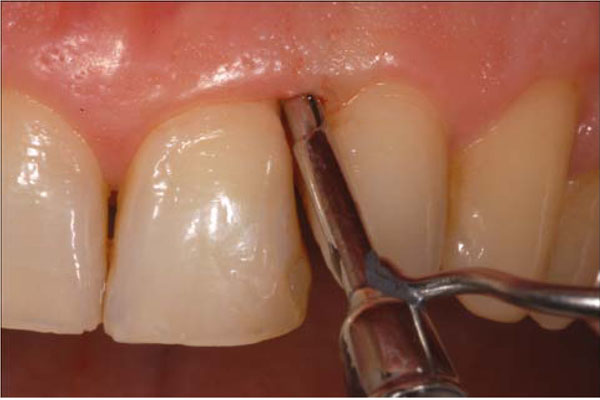

Examiner A using a standardized periodontal probe (CP11 Hu Friedy, Europe) detected: Plaque Index (PI) [9], Gingival Index (GI) [10], Probing Pocket Depth (PPD), and BOP (Fig. 2). The BOP was considered positive if bleeding occurred between 30 seconds after probing. Examiner B under endoscopic vision recorded the Endoscopic Biofilm Index (EBI) and the Endoscopic Calculus Index (ECI) at least 15 minutes later the preceding examination (Fig. 3) [11]. A time interval of 15 minutes was used in order to limit the possibility that the first exam, especially when bleeding was present, could affect the subsequent evaluation. The two endoscopic indices, reported on Table 1, have been recently purposed with the aim to distinguish different degrees and physical state of subgingival deposits.

Fig. (3).

Endoscopical visualsization of the subgingival area. The fiber is delivered to the gingival margin coupled into an instrument called “explorer”.